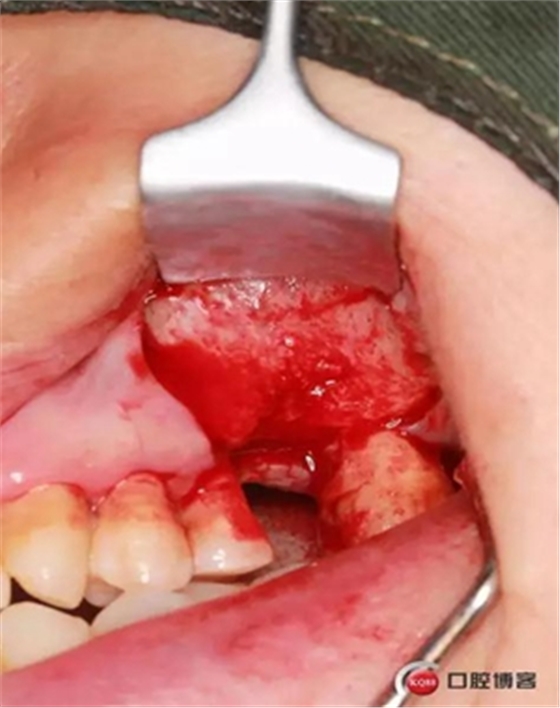

大家好,我是梁老師的助理小依。由于梁老師每天手術(shù)檔期安排較滿,加上經(jīng)常出差講課,沒有時間整理病例 。為了方便大家更及時的了解梁老師最新手術(shù)動態(tài),以后將由我為大家整理并推送梁老師最新經(jīng)典案例。案例文字旁白少,但圖片會盡量完整展示手術(shù)全過程,供大家學(xué)習(xí)參考。有任何問題,可以留言,梁老師會親自為大家解答。感謝大家對梁老師的支持和關(guān)注!